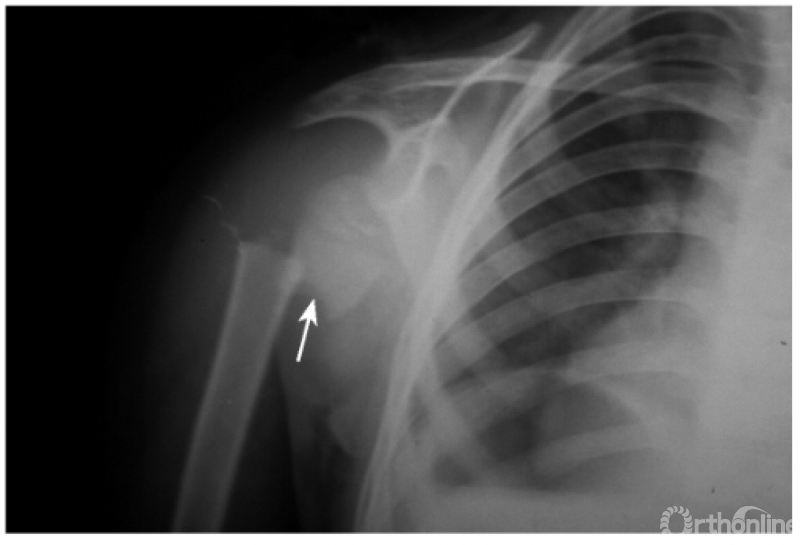

例7:肩关节盂下脱位并肱骨干骨折(本病常由于肱骨干骨折的干扰而最易漏诊肩关节的脱位)(如下图)。